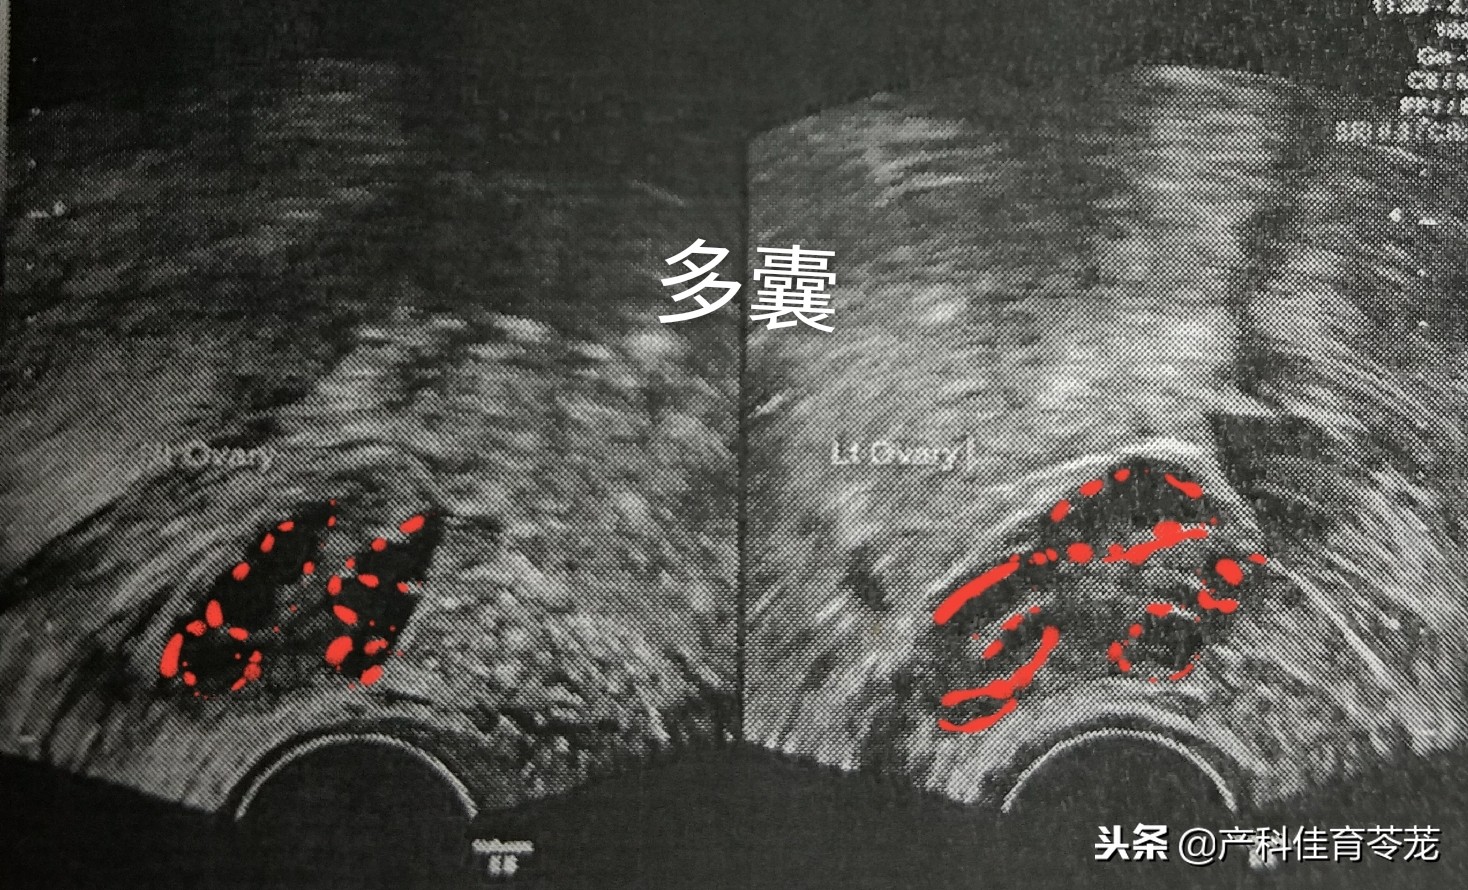

2、多囊卵巢

同样是卵巢增大,但B超图像是这样的:

可以看到卵巢内有很多个黑色的区域,专业术语称为“液性暗区”,其实是多了卵泡。

多囊卵巢属于内分泌紊乱,多数患者有闭经或者月经稀发(很长时间才来一次月经)、多毛、*疮痤**等雄激素增高的表现。

多囊卵巢的处理以调整周期、降雄激素、促排卵为主。